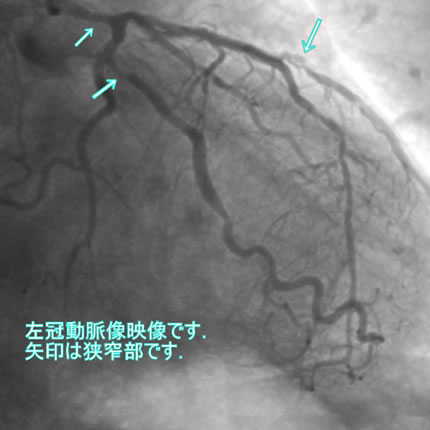

図1-2 左冠動脈造影像

図1-3 左冠動脈造影像

図1-4 左冠動脈造影像

図1-5 左冠動脈造影像

図1-6 左冠動脈造影像

図1-7 左冠動脈造影像

よく解らないと思いますが、冠動脈に多数の狭窄があることと冠動脈が「こぶ状変化(医学用語で瘤状変化)」を生じているのが解ると思います。

「#1: 50% #2 :50% #3 #4PD #4AV:75% #5 50% #6 75% #7 75% #8 #9 #10 #11 #12 」

#1 、#2 などの数字は冠動脈の部位を表します。50%というのは正常の50%が狭窄しているという意味です。